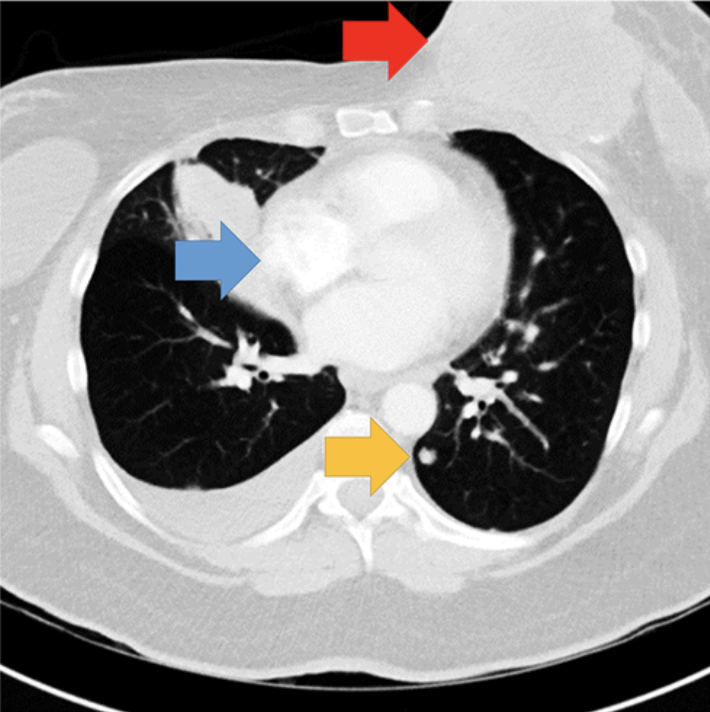

Single-slice of the chest CT showing the abnormalities. Arrows indicate the location of the breast mass (red arrow), lymphadenopathy (blue arrow), and a lung nodule (yellow arrow). Arrows not present in experimental display. Image courtesy of Psychonomic Bulletin & Review

So Williams, Drew and their colleagues from UCLA and Macquarie University set up another experiment. They asked 50 radiologists to evaluate seven chest CT scans for lung cancer, but this time the final scan included two clear abnormalities: a significant breast mass and a lymphadenopathy (an abnormal lymph node). Two-thirds of the radiologists did not notice the potentially cancerous mass. A third did not notice the lymphadenopathy.